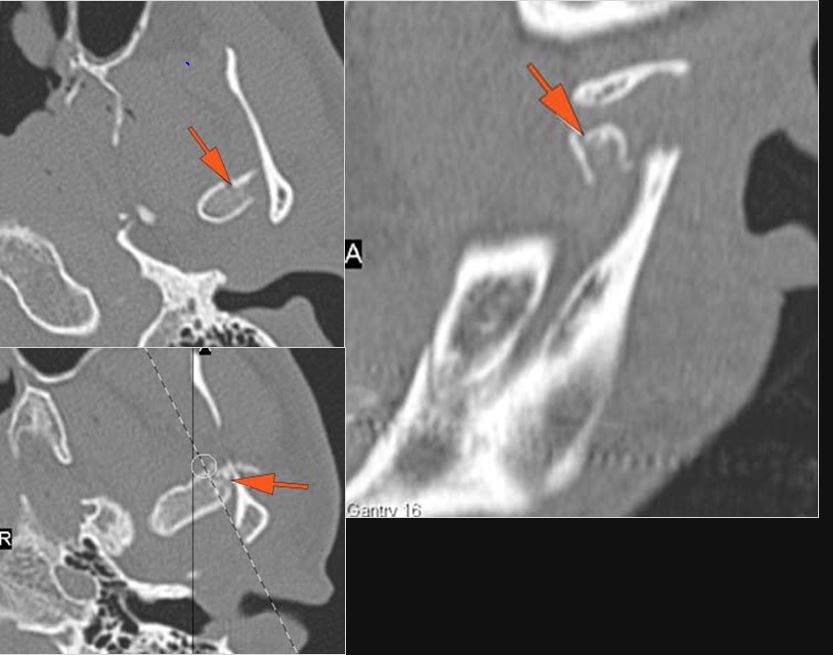

There is bony injury or displacement of the body, angle, ramus, parasymphyseal region, alveolar ridge, and condylar and coronoid process of the mandible. [In case of fracture, describe complexity and displacement].

There is entrapment of the muscles of mastication or other soft tissues by fractures of the coronoid process and/or zygomatic arch.

There is condylar fracture either within or outside of the joint capsule, or with or without involvement of the articular surface of the condylar head.